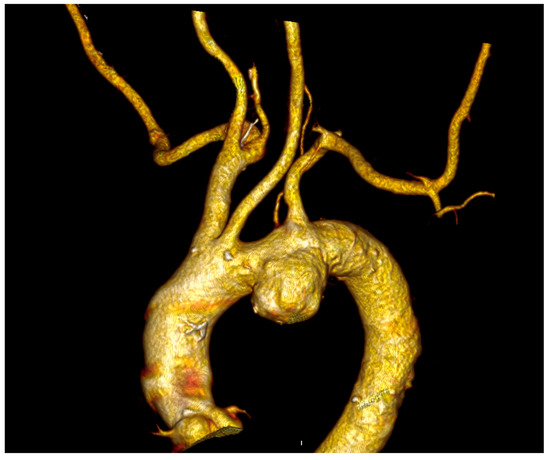

Endovascular revascularization was performed in a total of 94/149 (63%) patients:

• in situ fenestration (ISF) was selected in 3 patients (2%) (Figure 4).

Figure 4. Endovascular treatment of a type Stanford B aortic dissection using a zone II scalloped TEVAR in a patient treated at our institution and presenting with an isolated left vertebral artery (arrow) revascularized through the scallop designed to preserve flow in the left subclavian artery.